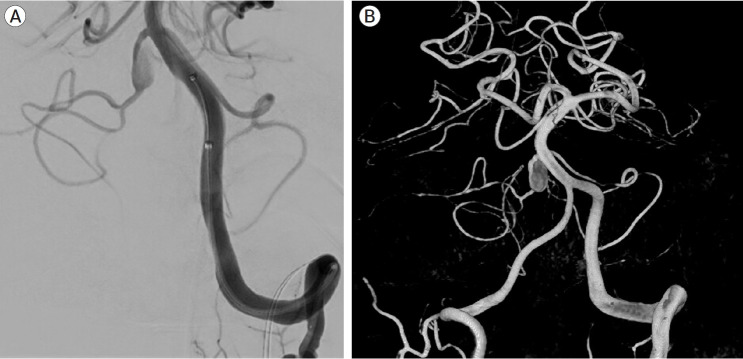

The Anterior Inferior Cerebellar Artery-Posterior Inferior Cerebellar Artery (AICA-PICA) common trunk is a rare variant of cerebral posterior circulation in which a single vessel originating from either the basilar or vertebral arteries supplies both cerebellum and brainstem territories. We present the first case of an unruptured right AICA-PICA aneurysm treated with flow diversion using a Shield-enhanced pipeline endovascular device (PED, VANTAGE Embolization Device with Shield Technology, Medtronic, Canada). We expand on this anatomic variant and review the relevant literature. A 39-year-old man presented to our treatment center with vertigo and right hypoacusis. The initial head CT/CTA was negative, but a 4-month follow-up MRI revealed a 9 mm fusiform dissecting aneurysm of the right AICA. The patient underwent a repeat head CTA and cerebral angiogram, which demonstrated the presence of an aneurysm on the proximal portion of an AICA-PICA anatomical variant. This was treated with an endovascular approach that included flow diversion via a PED equipped with Shield Technology. The patient's post-procedure period was uneventful, and he was discharged home after two days with an intact neurological status. The patient is still asymptomatic after a 7-month follow-up, with MR angiogram evidence of stable aneurysm obliteration and no ischemic lesions. Aneurysms of the AICA-PICA common trunk variants have a high morbidity risk due to the importance and extent of the territory vascularized by a single vessel. Endovascular treatment with flow diversion proved to be both safe and effective in obliterating unruptured cases.

小脑前下动脉-小脑后下动脉(AICA-PICA)共同干是大脑后循环的一种罕见变异,即由基底动脉或椎动脉的单一血管供应小脑和脑干区域。我们介绍了首例使用盾牌增强管道内血管装置(PED,加拿大美敦力公司的带盾牌技术的 VANTAGE 栓塞装置)进行血流分流治疗的未破裂右侧 AICA-PICA 动脉瘤病例。我们对这一解剖变异进行了详细阐述,并回顾了相关文献。一名 39 岁的男子因眩晕和右侧听力减退来到我们的治疗中心。最初的头部 CT/CTA 检查结果为阴性,但 4 个月后的磁共振成像检查发现右侧 AICA 有一个 9 毫米的纺锤形剥离动脉瘤。患者再次接受了头部CTA和脑血管造影检查,结果显示在AICA-PICA解剖变异的近端存在动脉瘤。患者接受了血管内治疗,包括通过装有盾牌技术的 PED 进行血流分流。患者术后恢复顺利,两天后出院回家,神经状况良好。经过 7 个月的随访,患者仍无症状,磁共振血管造影显示动脉瘤闭塞稳定,无缺血性病变。AICA-PICA 共干变异动脉瘤的发病风险很高,这是因为单根血管血管化区域的重要性和范围。事实证明,在未破裂的病例中,使用血流分流的血管内治疗既安全又有效。